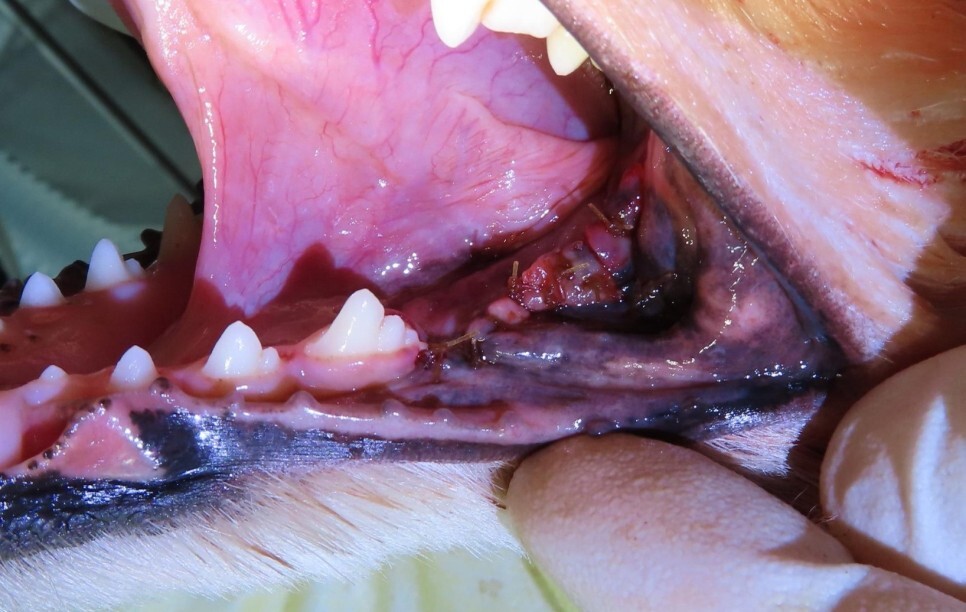

사진을 보면 치아 아래쪽 잇몸에 혹 비슷한 것이

관찰되고 있습니다.

이 아이의 경우 병변이 너무 많이 진행되어서 첫 번째

어금니와 두 번째 어금니 모두 발치를 진행하였습니다.